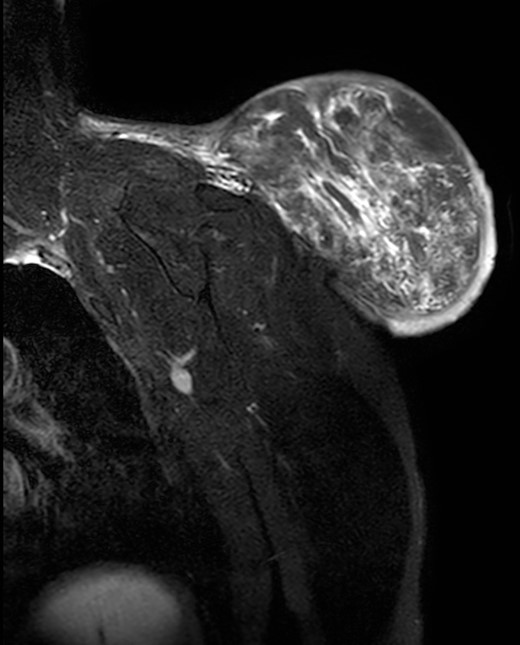

During the follow-up, a magnetic resonance (Figs 3 and 4) was performed describing a soft tissue lesion highly suggestive for liposarcoma as a first possibility diagnosis, with an addition image suggesting metastatic axillary lymph node. After the imaging results, biopsies were taken and analysed by the pathologist with a final diagnosis of PL.

Magnetic resonance imaging T2 with contrast: giant excrescent lesion of 19 × 18 × 14.4 cm of diameter located in the subcutaneous tissue of the posterior aspect of the scapula divided by multiple septums; axillary lymph node of ~0.9 cm; images compatible with liposarcoma with a metastatic axillary lymph node.